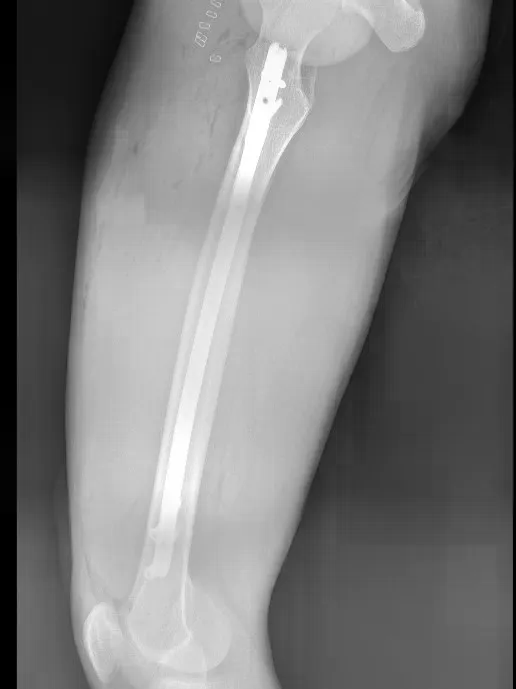

术后,在骨科医护团队的细心指导与护理下,康复科同步介入,为患者制定个性化康复功能锻炼方案并全程指导,加速肢体功能恢复,术后第2天即可在床上进行简单肢体活动,疼痛症状明显缓解;术后1周,床上膝关节活动度达90°,髋关节活动度90°,肢体功能逐步恢复。复查影像学显示,骨折端复位精准、内固定位置稳固,完全达到临床理想标准,为后续愈合奠定了坚实基础。

此次手术的成功,既彰显了我院多学科协作的高效联动能力,更凸显了骨科团队在复杂骨折治疗中“精准诊断、精湛操作、沉着应变”的硬核实力。面对股骨粗隆下骨折这一“臭名昭著”的难治性骨折,医院以快速响应为基础,以技术突破为核心,用“严丝合缝”的完美手术证明了综合诊疗实力。